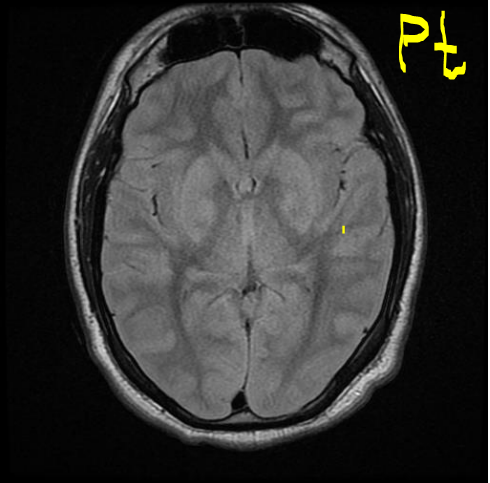

Case 3 Q# 1 of 4

• 61 year old man

• Presents with right arm and leg numbness and weakness and slurred speech.

• Symptoms lasted about 20 minutes and resolved

• PMHx: type I diabetes, hypertension, and hyperlipidemia

• Exam on presentation is normal. MRI is attached.

What is the etiology of his stroke / TIA?

Microemboli; specifically, from his thrombosed left internal coronary artery.

Case 3 Q# 2 of 4

How is the etiology of his stroke consistent with the MRI?

The MRI shows very tiny, punctate infarcts throughout several axial layers of the cortex that all appear to be in the same location sagitally/coronally, aka all in the territory of one small vessel! This supports a small embolus that occluded only the area of one small brain vessel.

Case 3 Q# 3 of 4

What about the MRI helps you rule out a lacunar infarct? What pathogenesis is typically responsible for lacunar infarct?

Lacunar infarcts tend to affect only deeper structures of the brain, and tend to measure 1-1.5cm (somewhat larger than this tiny punctate infarction).

Hyaline arteriolosclerosis typically precipitates lacunar strokes.